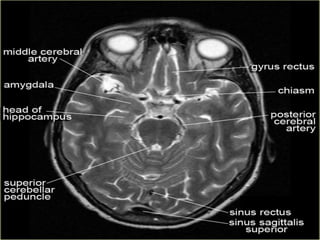

Antero-medial temporal lobes

Fig 2a: T1MRI axial projection. 1: inter- hemispheric scissure; 2: lateral sulcus; 3: frontal lobe; 4: insula lobe; 5: temporal lobe; 6: occipital lobe.